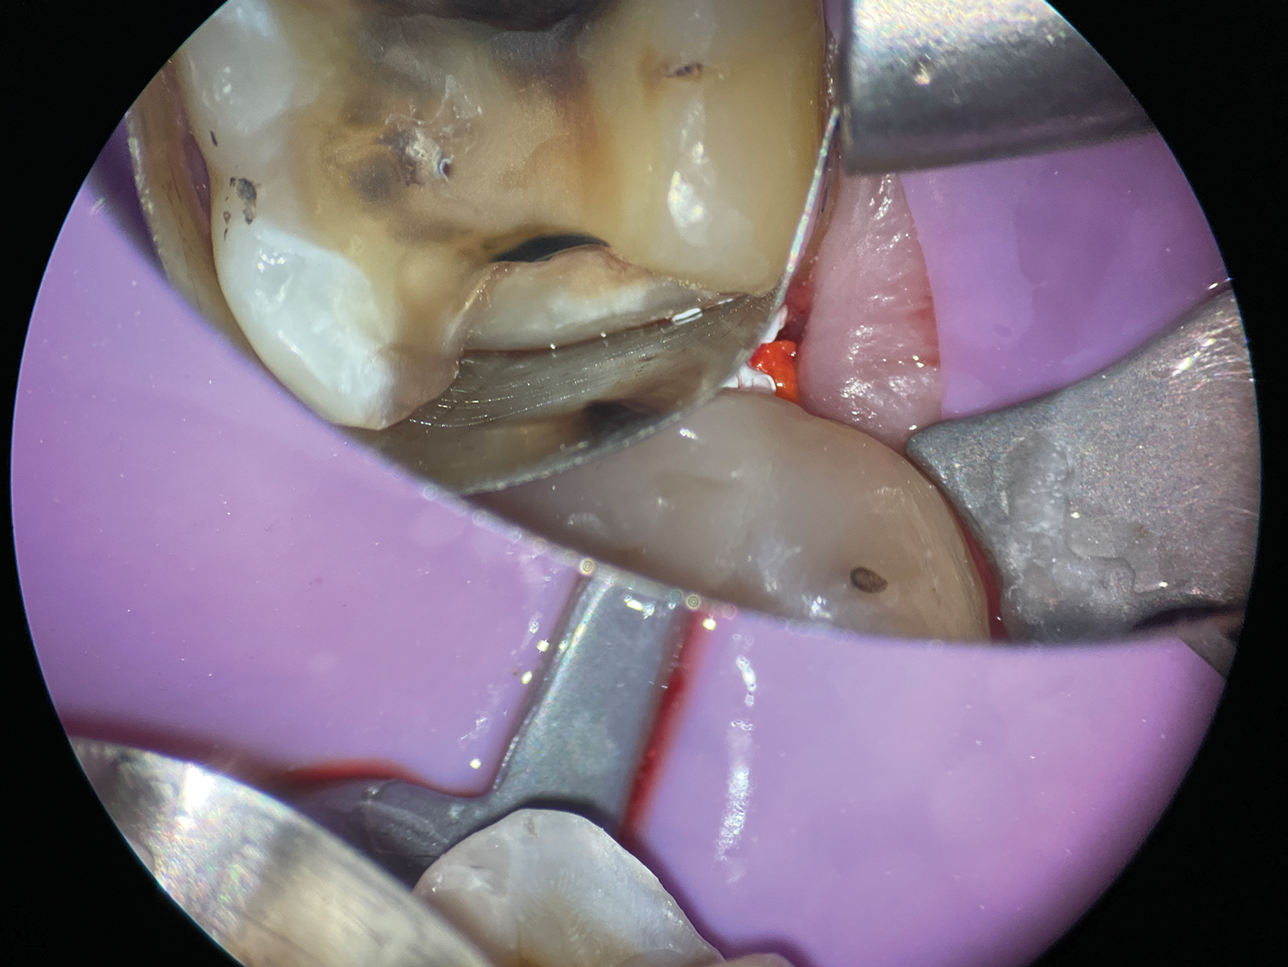

In cases involving extremely deep defects that extend to the bone level, achieving an adequate seal and proper isolation for adhesive procedures can be particularly challenging (Figure 10 and Figure 11). Oftentimes, a single matrix proves insufficient to reach the depth of such defects and effectively shield the cavity from contamination by saliva or blood (Figure 12).

The matrix-in-matrix technique provides a practical and effective solution for these cases (Figure 13). By introducing a second matrix within the first, more specifically, a copper band that has been carefully cut and positioned inside a conventional matrix, the seal is significantly enhanced. This dual-layered approach not only extends the matrix coverage to the full depth of the defect for isolation but also ensures stability in the critical treatment area.

(12.) After subgingival placement of a Tofflemire matrix, despite using a wedge and adding additional support with polytetrafluoroethylene tape, fluid infiltration persists through the matrix and margin.

Figure 12

(13.) A wide 2-mil copper band was placed as an additional matrix to create absolute isolation, effectively sealing the space between the Tofflemire matrix and the margin.

Figure 13